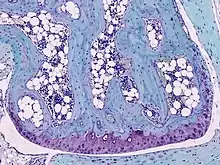

Light micrograph of undecalcified hyaline cartilage showing chondrocytes and organelles, lacunae and matrix.

Cartilage is composed of specialized cells called chondrocytes that produce a large amount of collagenous extracellular matrix, abundant ground substance that is rich in proteoglycan and elastin fibers. Cartilage is classified in three types, elastic cartilage, hyaline cartilage and fibrocartilage, which differ in relative amounts of collagen and proteoglycan.